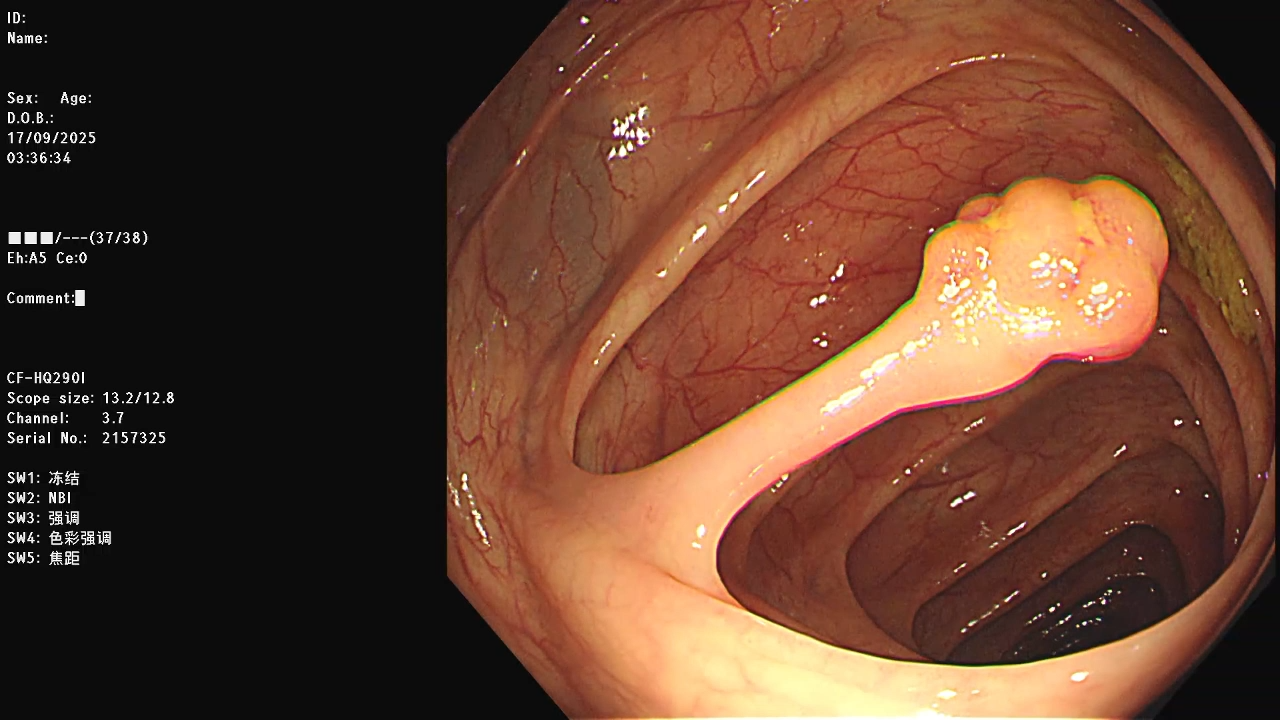

病例结肠长蒂息肉切除

这种长蒂息肉切除,都建议先用夹子把根部夹紧再切除,像视频中第一个夹子是没夹紧的,就要再打一个,粗蒂的同理,可以多打一两个,直到完全夹闭根部为止,同时可以观察到息肉颜色变成紫色。